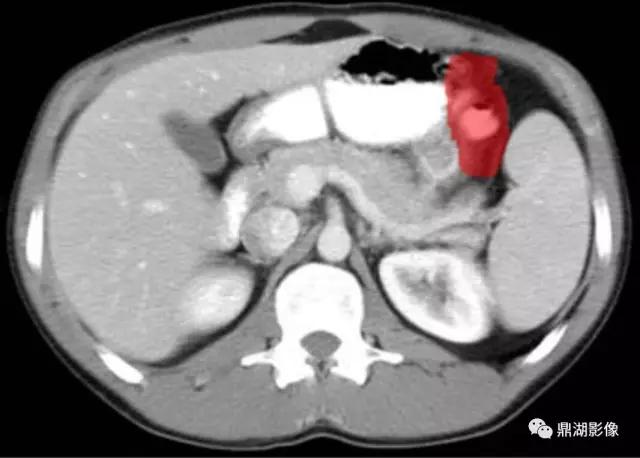

脾区(Splenic Flexure)

膈肌脚(Curs of Diaphragm)

下腔(Inferior Vena Cava)

十二指肠(Second Portion of the Duodenum)